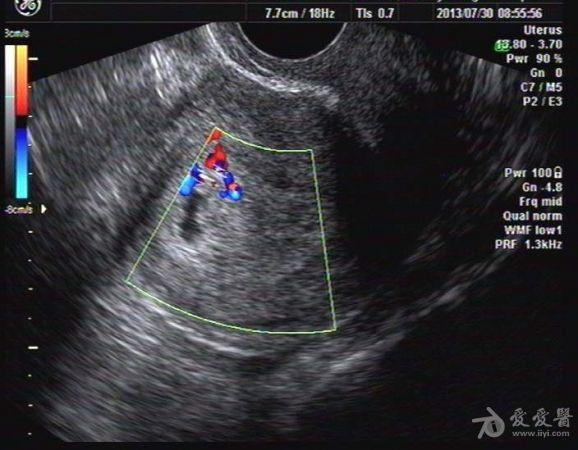

停经40天HCG(+) 我院B超:子宫大小56x48x61mm,宫内探及一大小9x4mm暗区,形态不规则,边缘不规整,内未见胚芽及胎心搏动。